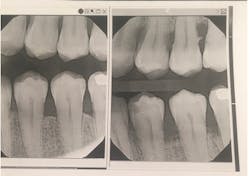

Periodontal probe depth may not be an indicator of active disease, unless active bleeding results following this probing. Sulcular epithelial ulcerations may be like small spots of rust on an otherwise intact rain gutter, or they can be broad swaths of pervasive rust (ulcers) sweeping across all surfaces. Using any of the standard periodontal probes, you may or may not hit one of the spotty ulcerations, and show minimal to no bleeding. This might give the evaluator a false sense of gingival health. I felt I needed a more comprehensive attempt to find ulcerated sulcular walls.